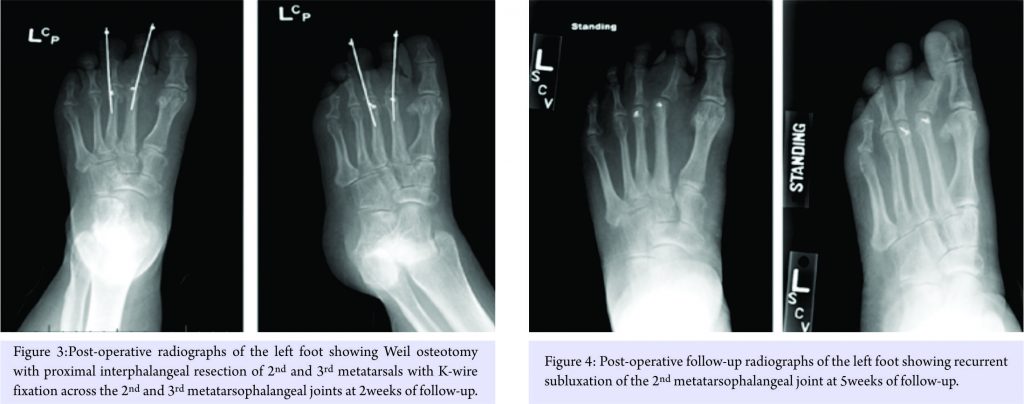

Treatment options were discussed with the patient, including surgical intervention for her foot problems. She was counseled about the high risk of post-operative recurrence of deformities, nonunion, wound complications, and worsening of pain (in setting of pre-existing neuropathy) because of the underlying syndrome. The patient was operated on first on the left foot for Morton’s neuroma excision and Weil osteotomy with proximal interphalangeal (PIP) joint resection of the second and third metatarsals with K-wire fixation across the second and third MTP joints (Fig. 3). Her post-operative course was complicated by recurrent subluxation of the second MTP joint (Fig. 4). A revision surgical option was discussed but refused by the patient, as she was satisfied with the surgery in terms of good pain relief and functional improvement.

Following 7-week post-operative recovery period from the left foot surgery, the patient underwent Morton’s neuroma excision and Weil osteotomy with second and third PIP resection and K-wire fixation in the right foot (Fig. 5). Extensor tendon lengthening was also performed in the same foot. Post-operative course was complicated by atrophic nonunion of the osteotomies (Fig. 6), as well as worsening of her neuropathic pain.